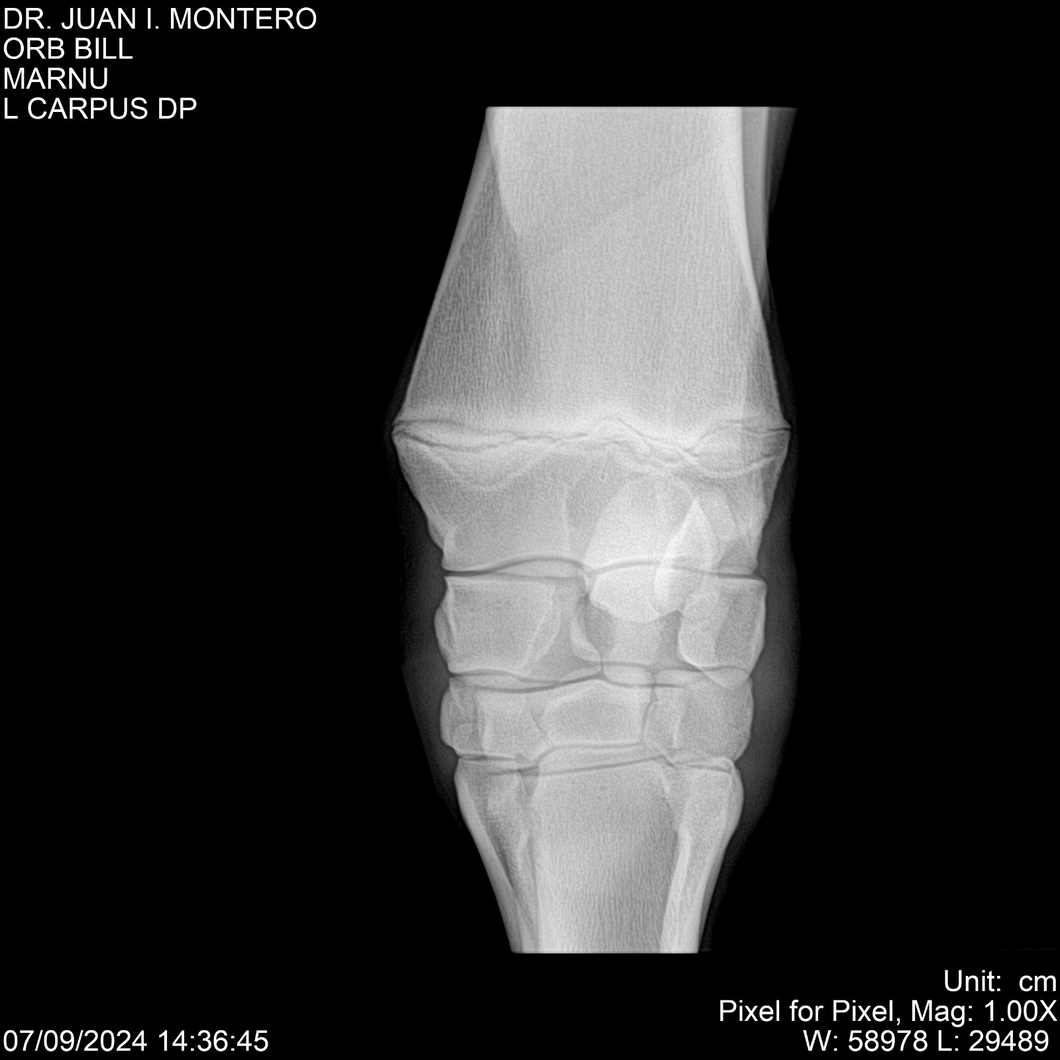

LOTE 7, ORB BILL 🔥 🔥 🔥 Lote Anterior Volver al remate Lote Siguiente Ficha Contacto Montevideo - Ficha del Lote Identificador: #282523 Categoría: Yeguarizos Montevideo - 83 Visualizaciones ClicData Contacto Empresa: Abelenda N. R., Walter Hugo Nombre*: Teléfono* : E-mail* : Mensaje Enviar Registrese gratis Este contenido Exclusivo está disponible sólo para usuarios registrados Ingresar